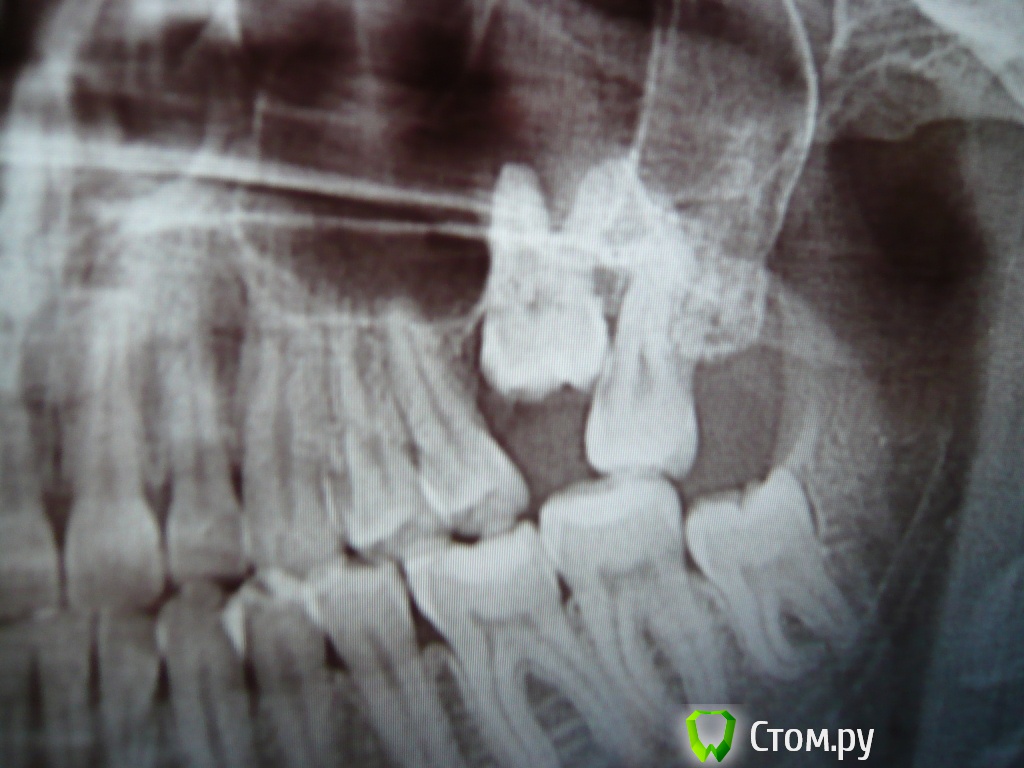

Доброго времени суток! Мне 23 года. Есть верхняя левая 6-ка, из под десны вылезла на ~ 3 мм. Уважаемые специалисты, прошу ответить на 2 вопроса: 1) целесообразно ли удалить верхнюю левую 7-ку с целью освобождения места для полноценного прорезывания 6-ки? 2) Какова вероятность естественного (без брекет-лечения) полного прорезывания 6-ки? Давно уже мучаюсь с 6-кой и 7-кой, не болят, постепенно появляется налет в области этих зубов, полноценная прочистка затруднительна, неприятный (тухлый) привкус в области этих зубов. Хочу разрешить проблему раз и на всегда. Заранее спасибо.